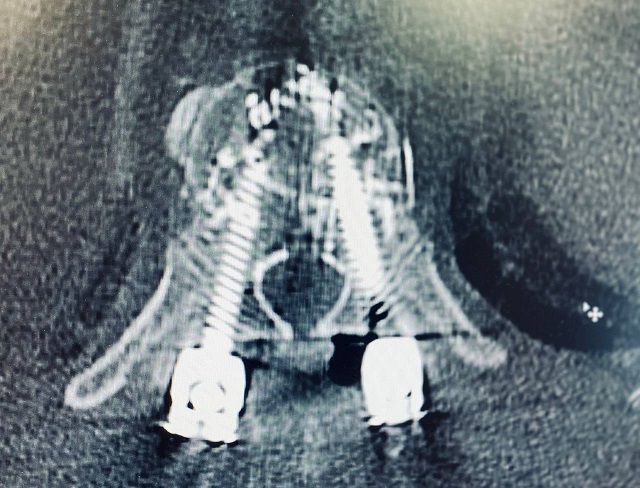

Сложнейшую операцию врачи провели при помощи новейшей технологии free hand. Им удалось установить в позвоночник восемь титановых винтов, которые вследствие скрепили между собой «цементом».

Фото: телеграм-канал «БСМП Челны»